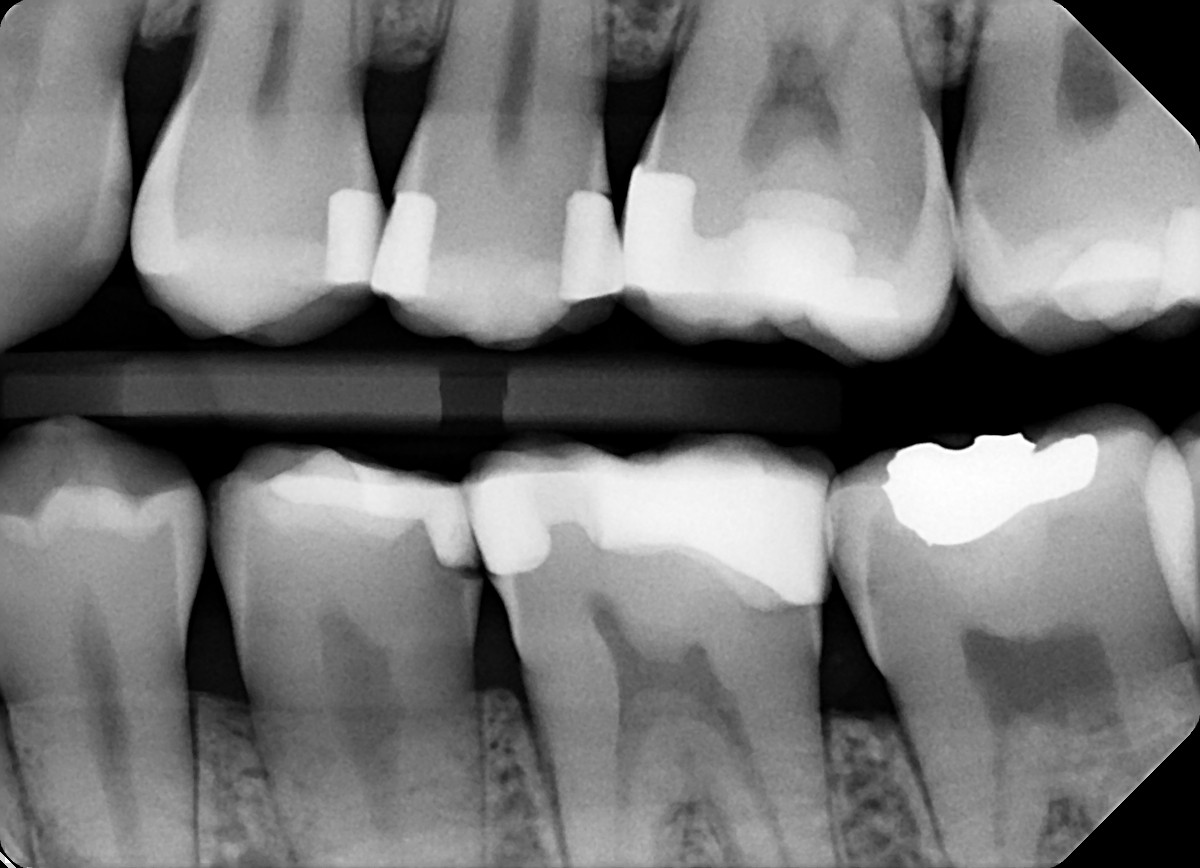

18 / 35

18. On which surface a recurrent caries can be detected?

crowns mostly show open margin not recurrent caries

19 / 35

19. On which surface a recurrent caries can be detected?

This is the PA X ray of the question # 18, based on this X ray recurrent X ray for distal tooth # 3.7 can also be selected